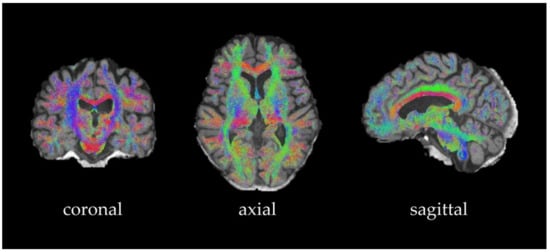

3.2. Generation of Streamlines and the Structural Connectivity Matrix